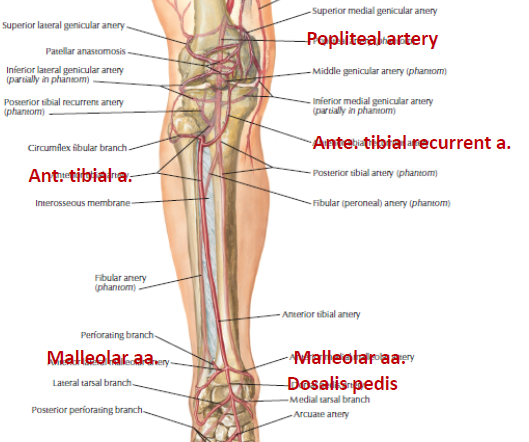

flowchart TB F[femoral a.]-->Pp[popliteal a.]-->ah((adductor<br>hiatus)) ah-->pt[Post. tibial a.] pt-->f[Fibular a.]-->t[小腿外側] ah-->at[Ant. tibial a.] at-->atr[Ant. tibial<br>recurrent a.]-->k[Knee] at-->m[Malleolar a.] at-->d[Dosalis pedis]